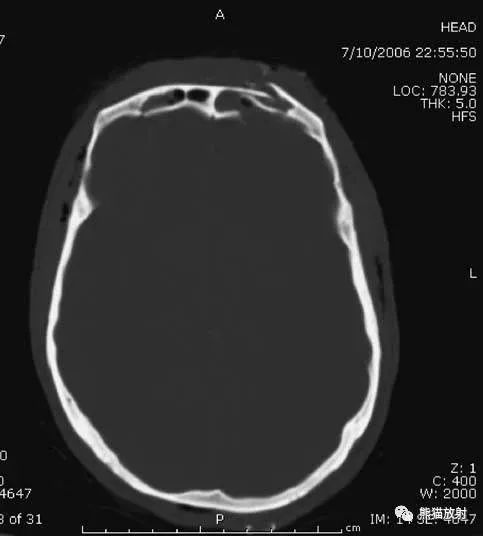

1、颅骨骨折

▲额骨骨折:左侧额窦内外侧壁骨折。

▲左侧颞骨骨折。